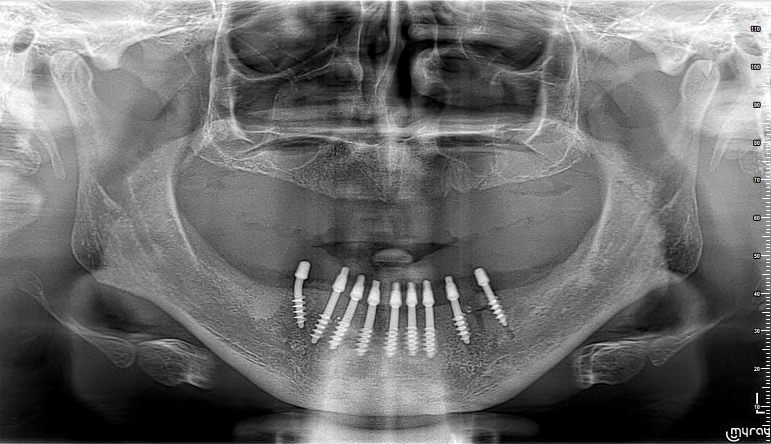

![/userfiles/files/02-cortico-basal-implants.jpg [/userfiles/files/02-cortico-basal-implants.jpg]](/userfiles/files/02-cortico-basal-implants.jpg)

Друг случай на напълно обеззъбена долна челюст при млад човек на видима възраст около 40 години. Имаше износена долна тотална плакова протеза, с която се чувстваше дискомфортно.

Както се вижда от ортопантомографията, поставени са 9 кортико базални имплантата